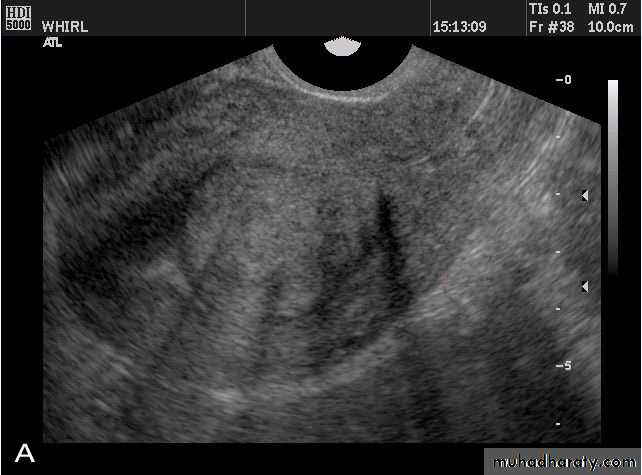

Transabdominal scanned image

• Rupture of hemorrhagic ovarian cyst:

Transvaginal scanned image